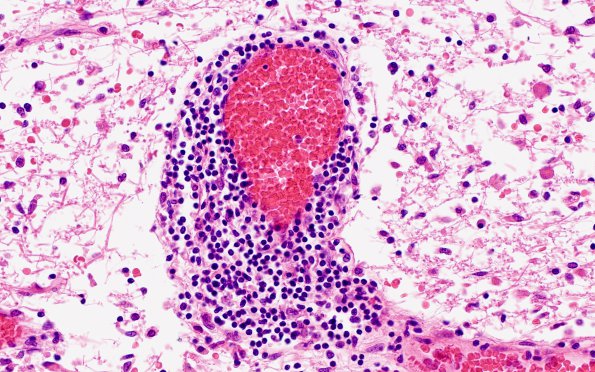

Mature perivascular lymphocytes within pale, gliotic white matter (H&E)